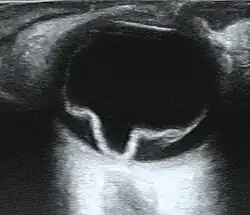

| Cross section of retinal detachment | |

If the view of the retina is not clear, imaging techniques such as ultrawide-field fundus photography, B-scan ultrasonography, and optical coherence tomography (OCT) may help to identify a detachment.[8][13][14] Fundus photography provides a detailed view of the back of the eye, potentially revealing retinal tears or breaks.[8][16] On B-scan ultrasonography, a detached retina typically appears as a membrane floating in the vitreous cavity, moving in a wave-like motion.[19] OCT can detect fluid behind the retina, involvement of the macula (the central part of the retina), and other abnormalities within the retinal layers.[8][20]